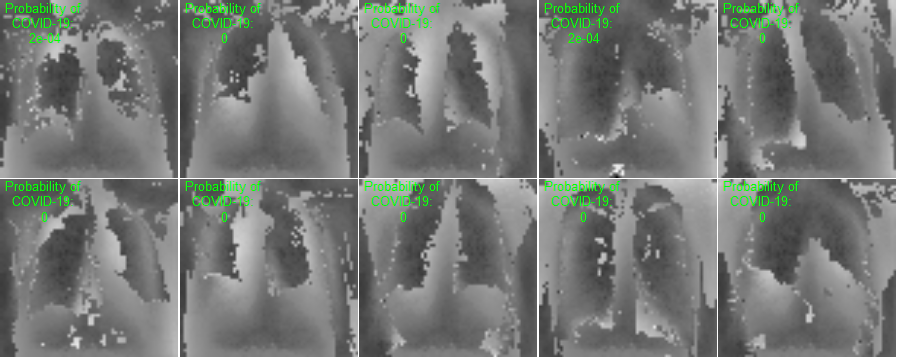

This section presents visualization of the proposed architecture. These visualizations are presented in Figure 5. Unlike Figure 2 that is an executive summary with each position representing many samples, these visualizations in Figure 5 are sample-wise plots. In other words, the 10 original images that are sized 128 by 128 in Panel A and Panel B are the same samples in the second row, 1st Conv. Layer, and the third row, 2nd Conv. Layer.

Visualization Interpretation The plot in Figure 5 of the original images for COVID-19 patients has grey and cloudy textures in chest area. Because an X-ray picture is at its brightest when most of the light beams emitted are bounced back from the object, we can observe bones to be the color “white” while the margin to be completely “black”. For muscle and organs inside human body, X-ray beams that are emitted can only partially be collected and this causes the greyscale on the X-ray images in chest area. For COVID-19 patients, there are grey and shaded area in the chest X-ray pictures. This is due to the inflammatory fluid when patients exhibit pneumonia-like symptoms. The fluid inside chest area is a consequence of human immune system fighting against outside diseases. This shaded (as seen in Panel A of Figure 5) prevents us from observing the clear location of lungs. This is different in Panel B where the lung areas are dark and almost black, because a healthy lung is filled with air (i.e. normal cases and X-ray image presents color black). The black and white contrast in the two panels is directly related to how much inflammatory fluid there is in human lungs. This contrast translates to greyscale on pictures and it is directly related with COVID cases and non-COVID cases (i.e. response variable ). The same contrast can be seen using the new variables (these are ’s based on equation 4) in the 1st Conv. Layer (sized 61 by 61). For COVID-19 patients, the lung area is cloudy and unclear while the healthy cases it is clearly visible. This is not a surprising coincidence because the proposed new variable modules, ’s, are engineered using equation 4 which relies on the response variable in training set. The images sized 61 by 61 from the proposed algorithm is a direct translation of not only the original pixels but also response variable. In other words, this visualization presents how I-score sees image data.

| Row (a) |  |

|

| 1st Conv. Layer: 61 by 61 | 1st Conv. Layer: 61 by 61 | |

| (Starting Point = 6, Window 2 by 2, Stride = 2) | (Starting Point = 6, Window 2 by 2, Stride = 2) | |

| Remark: variables | Remark: variables | |

| Same 10 images above with 3,721 variables | Same 10 images above with 3,721 variables | |

| Labels predicted using Model 1 | Labels predicted using Model 1 | |

| Row (b) |  |

|

Discussion for Figure 5.

This figure presents visualization summary for 10 randomly sampled images from COVID class and non-COVID class (each has 10). Panel A is for COVID patients and Panel B is non-COVID people. The first row plots the original images that are sized 128 by 128. The 1st Conv. Layer generates new variables. We plot the same 10 images from both classes using these 3,721 variables in the second row. We also print the predicted COVID probabilities on top left corner of each image. The 2nd Conv. Layer generate variables. We plot the same 10 image samples from both classes using these 900 variables in the third row. We also print the predicted COVID probabilities on top left corner of each image assuming using only these 900 variables as predictors. The plot of the original images for COVID-19 patients has grey and cloudy textures in chest area. This is due to inflammatory fluid when patients exhibit pneumonia-like symptoms. This shaded (as seen in Panel A) prevents us from observing the clear location of lungs. This is different in Panel B where the lung areas are dark and almost black which means the lung is filled with air (i.e. normal cases). The black white contrast in the two panels is directly related to how much inflammatory fluid there is in human lungs which translate to greyscale on pictures. The same contrast can be seen using the new variables (these are ’s based on equation 4) in the 1st Conv. Layer (sized 61 by 61). For COVID-19 patients, the lung area is cloudy and unclear while the healthy cases it is clearly visible.

|

Discussion for Figure 5.

Original Images to 1st Conv. Layer. The input images are sized 128 by 128. With the 1st Conv. Layer constructed, we have new variables. We trace back to the same samples as shown in the first row of Figure 5 and use these 3,721 variables only. When we plot these samples with these new variables, we resize them back in matrix form of 61 by 61. Panel A is for COVID class and Panel B is for non-COVID class. In addition, we use Model 1 in Table 4 to produce the texts that states predicted probability of COVID class. The red color implies ground truth to be COVID class (Panel A) and the green color implies ground truth to be non-COVID class (Panel B).

1st Conv. Layer. to 2nd Conv. Layer. From the resulting matrix of the 1st Conv. Layer, we are left with 3,721 variables. We go through the proposed design in Table 4 and we create a new convolutional layer, i.e. 2nd Conv. Layer. This new layer has variables. We take the same 10 sampled images from before and we use these 900 variables to present these images. In this presentation, we resize these 900 variables into shape 30 by 30. In other words, we get a smaller matrix that we can plot that exhibit mini version of similar patterns as before. We use Model 4 to generated the predicted probabilities. These probabilities are printed on the top left corner of each image and they are color coded similarly as before (red probabilities have ground truth of COVID class while green probabilities have ground truth of non-COVID class).